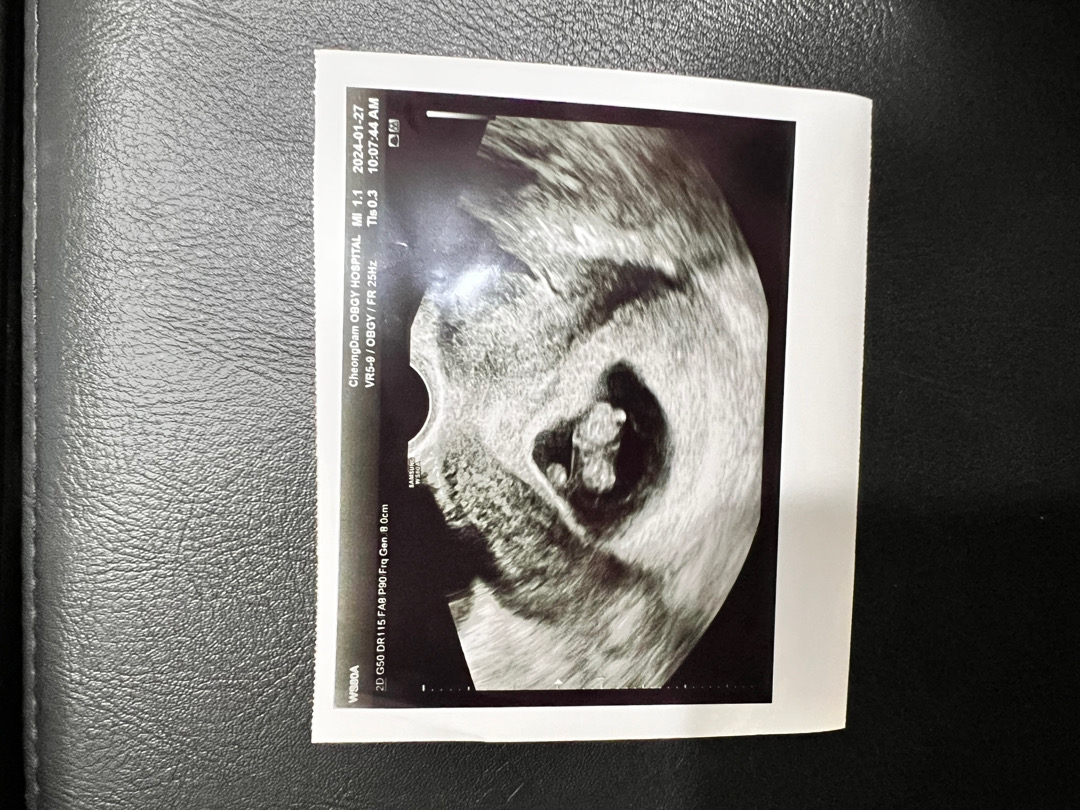

9주차 젤리곰~!

사진은 8주 4일차에 본 우래기 입니당 팔다리 움찔거리는거 너무 귀여웠어요 그런데 많이 움직이진 않아서 아쉬웠어요 다음엔 초코우유 필수!!!! 오늘로 9주1일인데 배 만져보니까 왼쪽에 동글딴딴한 자궁이 만져져요!! 입덧과 컨디션 난조는 점점 심해지네요ㅠㅠ 같이 화이팅 합시당 어머님들🩷🩷